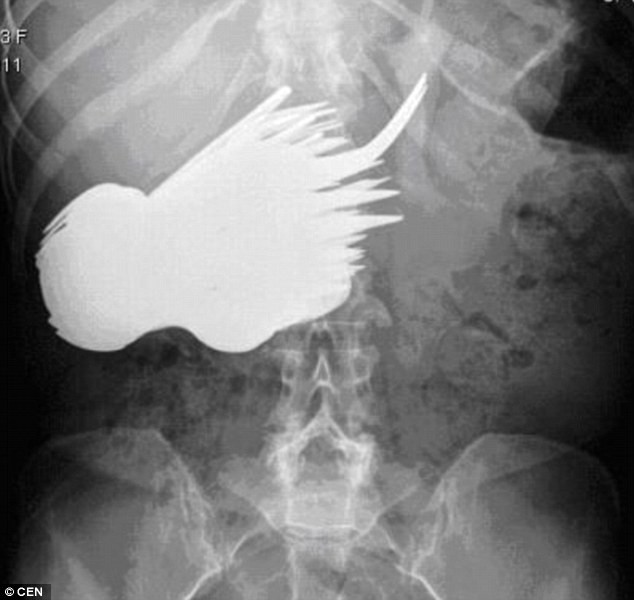

7. Alat makan

Sebanyak 78 item sendok dan garpu ditemukan dalam tubuh perempuan 52 tahun, Margaret Daalman. Menurut petugas medis yang menangani operasi, Daalman tampaknya telah menderita semacam obsesi dan setiap kali dia duduk untuk makan dia akan mengabaikan makanan dan justru makan peralatannya. Operasi dilakukan di Rotterdam, Belanda.